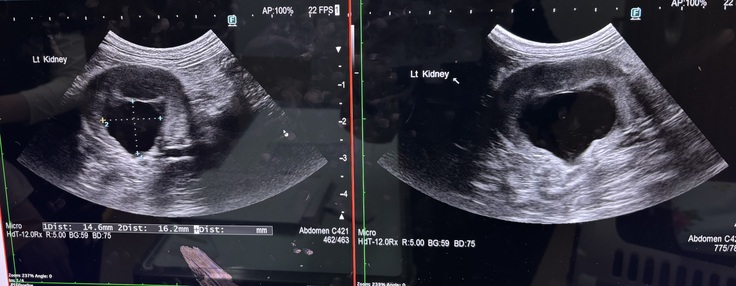

5月12日定期診察を受けてきました。

5月12日に骨盤骨折の術後経過と腎臓のエコー検査、血液検査を受けてきました。

骨折の方は順調に回復しており、腎臓も片腎ながら機能している右の腎臓には今のところ大きな問題はないとの診断をいただきました。

血液検査もNa値が高いですが、許容範囲内ということで安心いたしました。